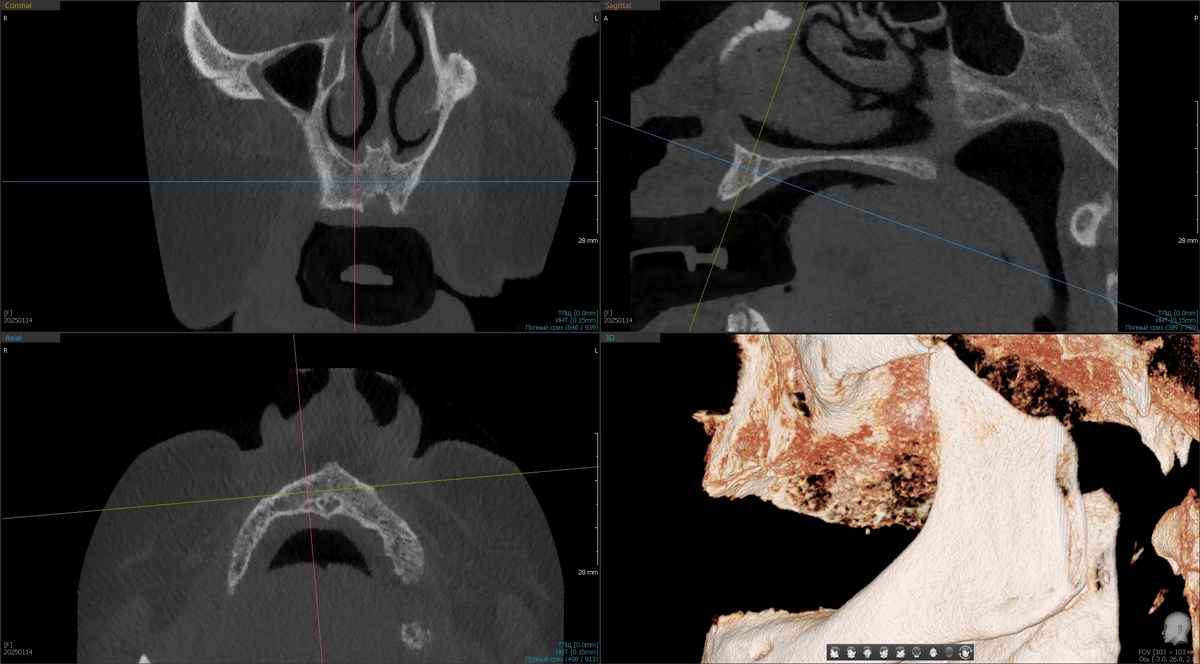

Дале оценка КЛКТ - есть ли место для имплантатов. На этом этапе, увы, с некоторыми пациентами приходится расставаться. Рассмотрим именно верхнюю челюсть, потому что с нижней проблем почти не бывает. Листайте:

Кости не очень много, но она есть и у доктора имеются интересные варианты для реабилитации.

Далее делаем КЛКТ с установленными в полость рта протезами и маячками:

Рентгеноконтрастные маячки, визуализация КЛКТ